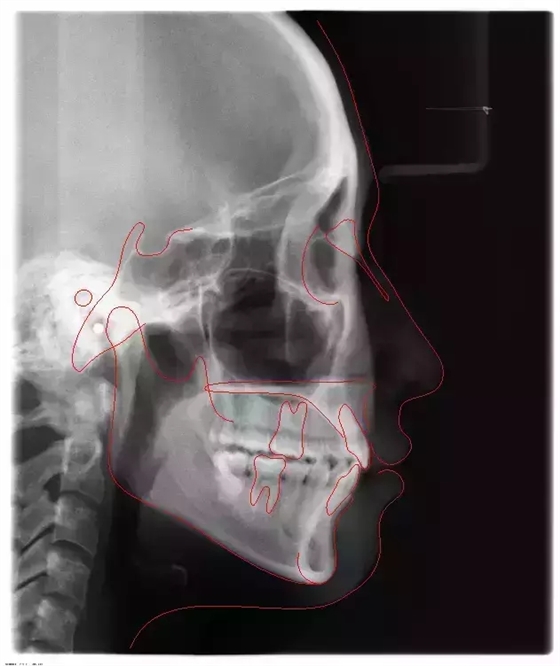

上下牙列擁擠,磨牙尖牙Ⅱ 類關(guān)系,3 度的深覆牙合,上頜中切牙伸長內(nèi)傾拔除上頜雙側(cè)的第一前磨牙,先粘上頜高轉(zhuǎn)矩的自鎖托槽排齊牙列,唇向開展上頜切牙,有一定的覆蓋,粘下頜標準轉(zhuǎn)矩托槽,上頜 1, 2 之間植入種植支抗壓入,同時后牙 5, 6 之間植入種植支抗內(nèi)收前牙,打開咬合關(guān)閉間隙。治療關(guān)鍵:前牙轉(zhuǎn)矩的控制第 1 個月 上頜粘上 Damon Q 高轉(zhuǎn)矩托槽,上 .014 熱激活 NiTi 絲。第 3 個月 上換 .014 x .025 熱激活 NiTi 絲。第 5 個月 上頜基本排齊,覆蓋增大,上換 .017 x .025 NiTi絲,下頜粘托槽,下 .014 熱激活 NiTi 絲。第 7 個月 上 .017 x .025 NiTi 絲加搖椅,下?lián)Q .014 x .025 熱激活 NiTi 絲第 9 個月 上頜換 .019 x .025 NiTi 絲加搖椅,下頜換 .017 x .025 NiTi 絲第 11 個月 下頜換 .019 x .025 加搖椅,上頜 1, 2 之間, 5, 6 之間植入種植釘,下頜出現(xiàn)散隙。第 13 個月 上頜換 .019 x .025ss 加搖椅,前牙種植釘用 Power Chain 壓低前牙(每側(cè) 100g),后牙種植釘關(guān)閉間隙(每側(cè) 150g),下?lián)Q .019 x .025ss,Power Chain 關(guān)閉間隙。第 19 個月 上頜前牙基本壓低到位去除前牙種植釘,繼續(xù)用關(guān)閉間隙,下頜散隙關(guān)閉。

第 22 個月 上頜覆蓋變小,去除 5, 6 之間種植釘,后牙前移關(guān)閉間隙。第 30 個月 患者未配合中線牽引,下中線仍有 1mm 右偏,患者對矯治效果滿意要求拆除,拆除固定矯治器,取模制作壓模保持器。 1.骨性 Ⅱ 類的患者內(nèi)收前牙時需對上頜前牙的轉(zhuǎn)矩進行較好的控制才能獲得良好的面型和唇部形態(tài)。 2.露齦笑的患者治療前要分析其病因是唇、牙齦、牙齒、牙槽骨、上頜骨或多種因素結(jié)合,再制定矯治方案。 3.Ⅱ 類第二分類伴露齦笑的患者的上頜前牙移動軌跡是唇向開展-壓低-整體內(nèi)收。 4.Ⅱ 類第二分類牙齒舌傾比較厲害的情況,上頜中切牙慎用樹脂咬合墊。 5.壓低前牙或控根移動時容易發(fā)生牙根的吸收,需輕力緩慢的移動。